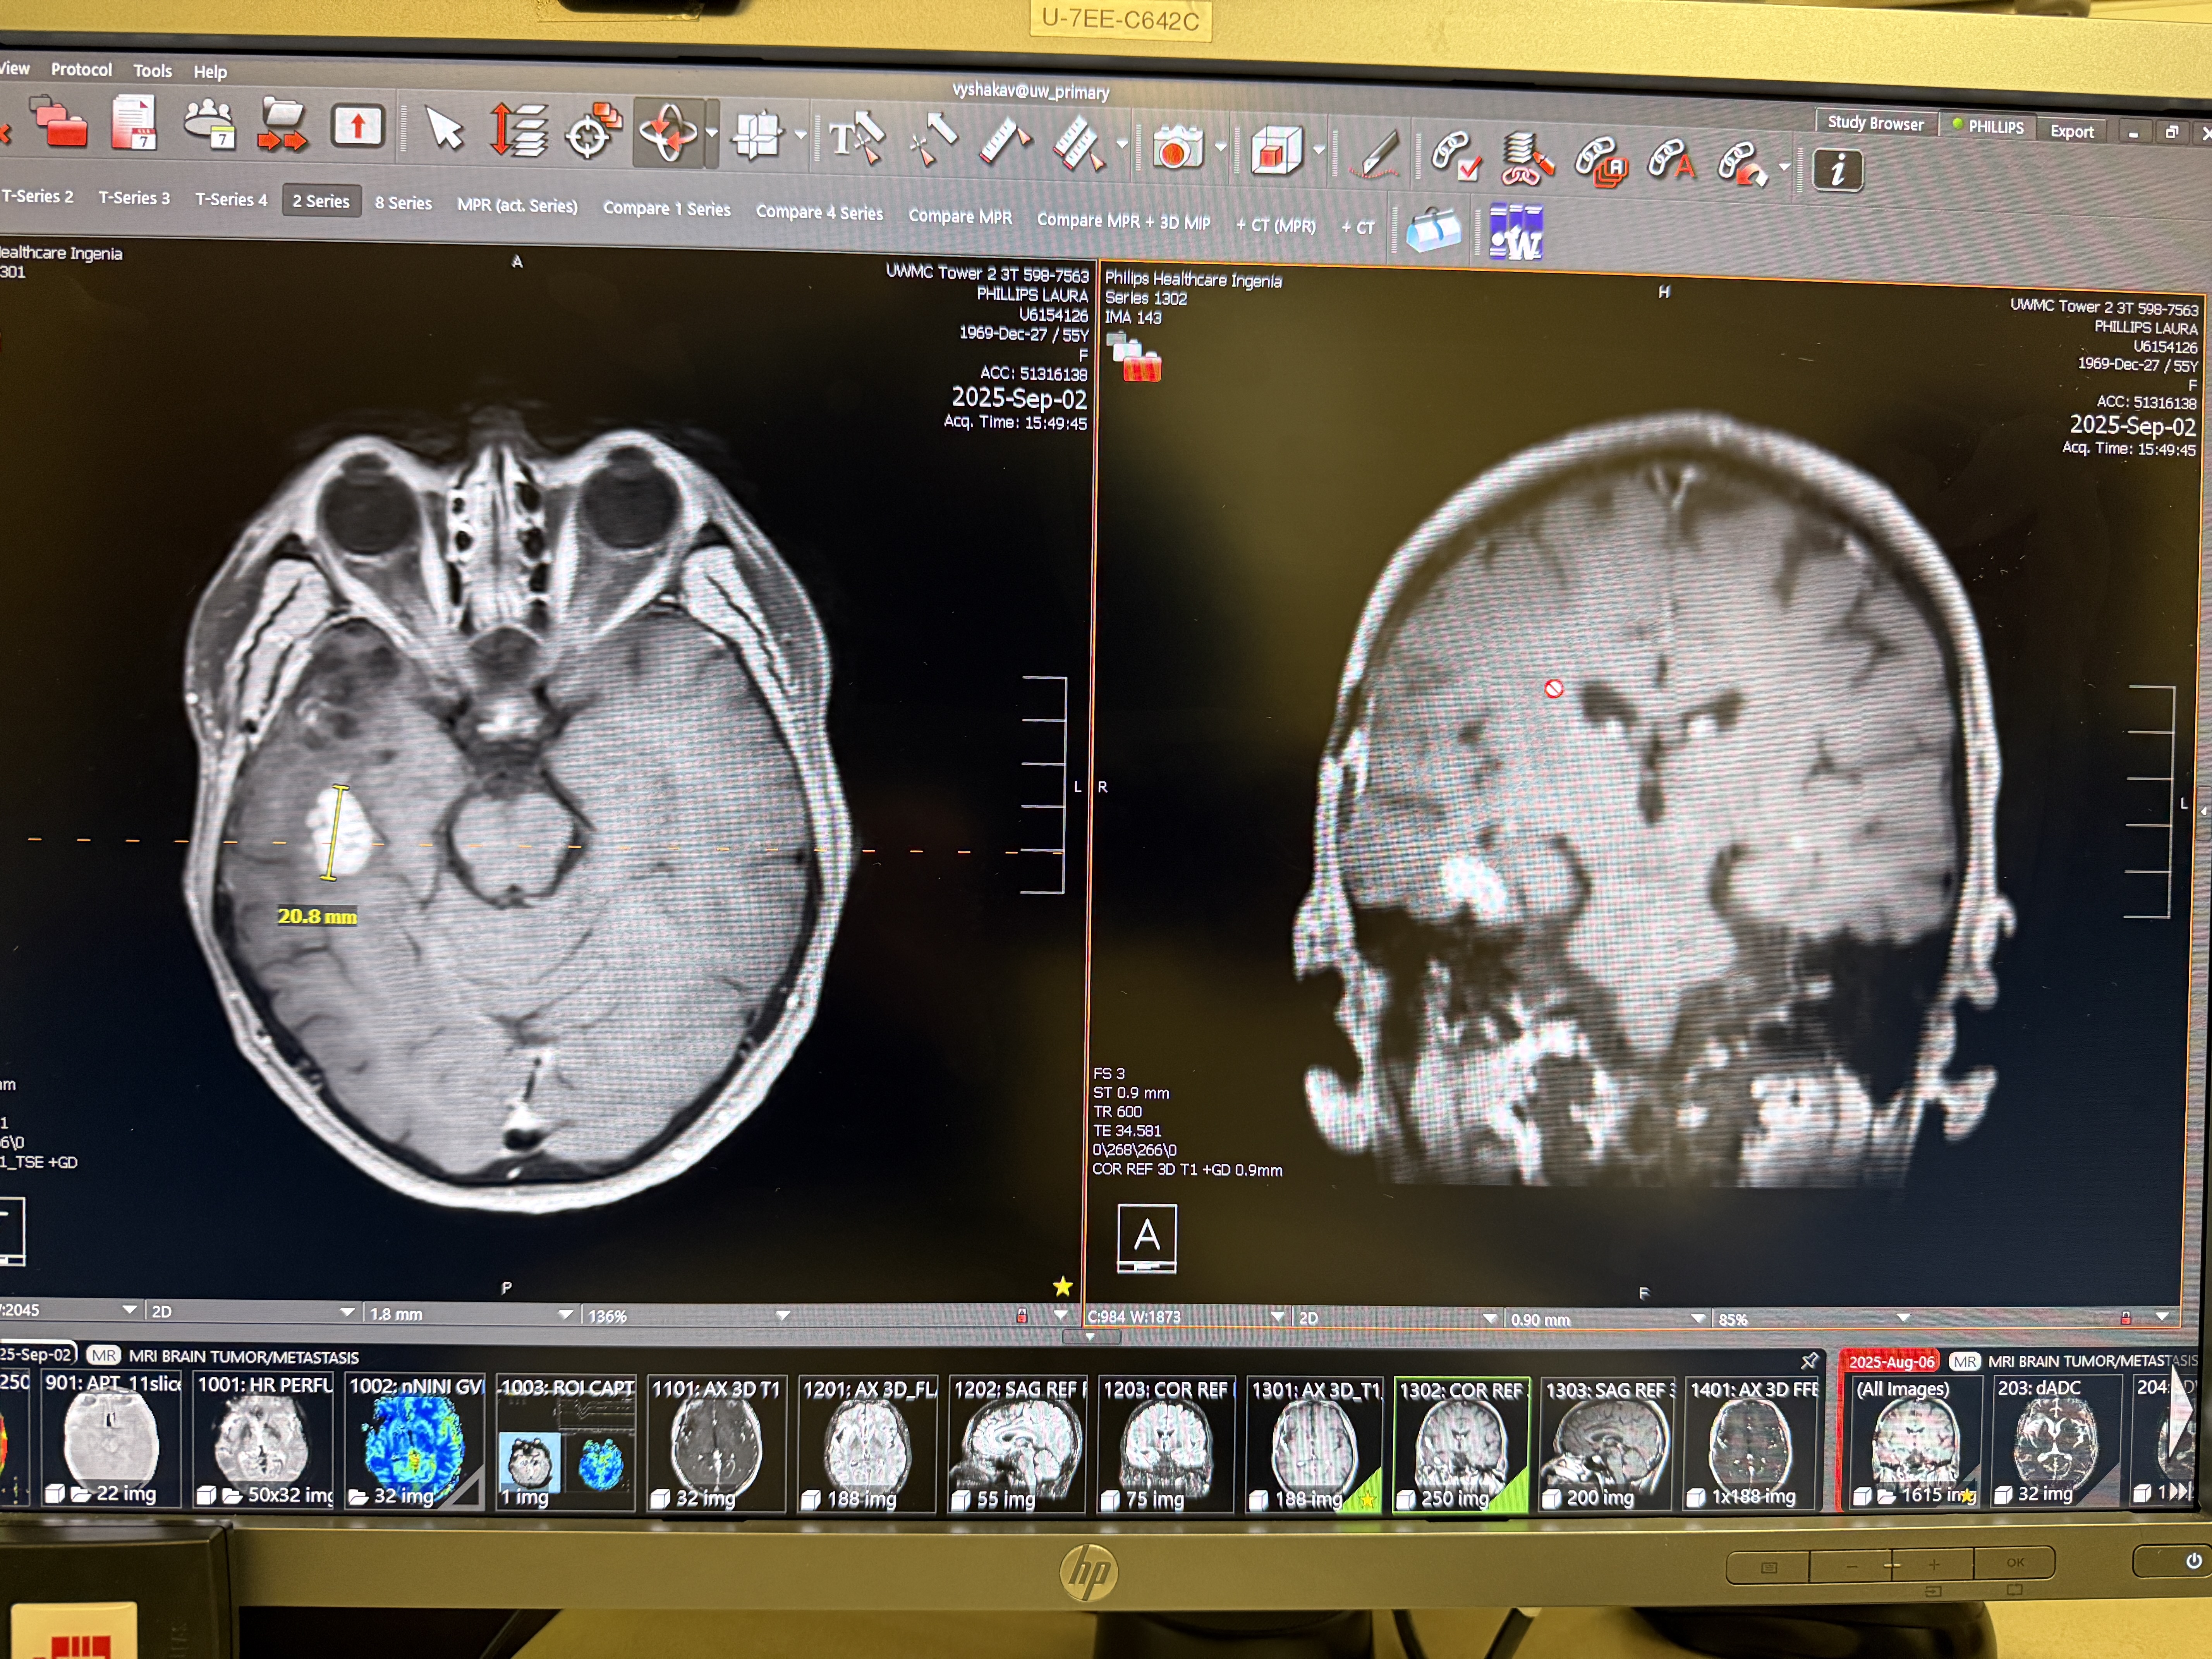

This leads us to today. We got a new MRI on September 2nd (2 days ago) and visited the doctor this morning. He showed us the images of the new MRI which did show a slight increase in the size of the affected area, but no new blood vessel growth in the new scan.

He did say that the lack of new blood vessels combined with the lack of any new symptoms was a very encouraging sign that this is likely just an affected area.

In the first image, you can see the spot on the left side of the image (right side of the brain since the images are reversed), but on the second image, you can see the area where the spot is does NOT show any highlights or additional blood flow.